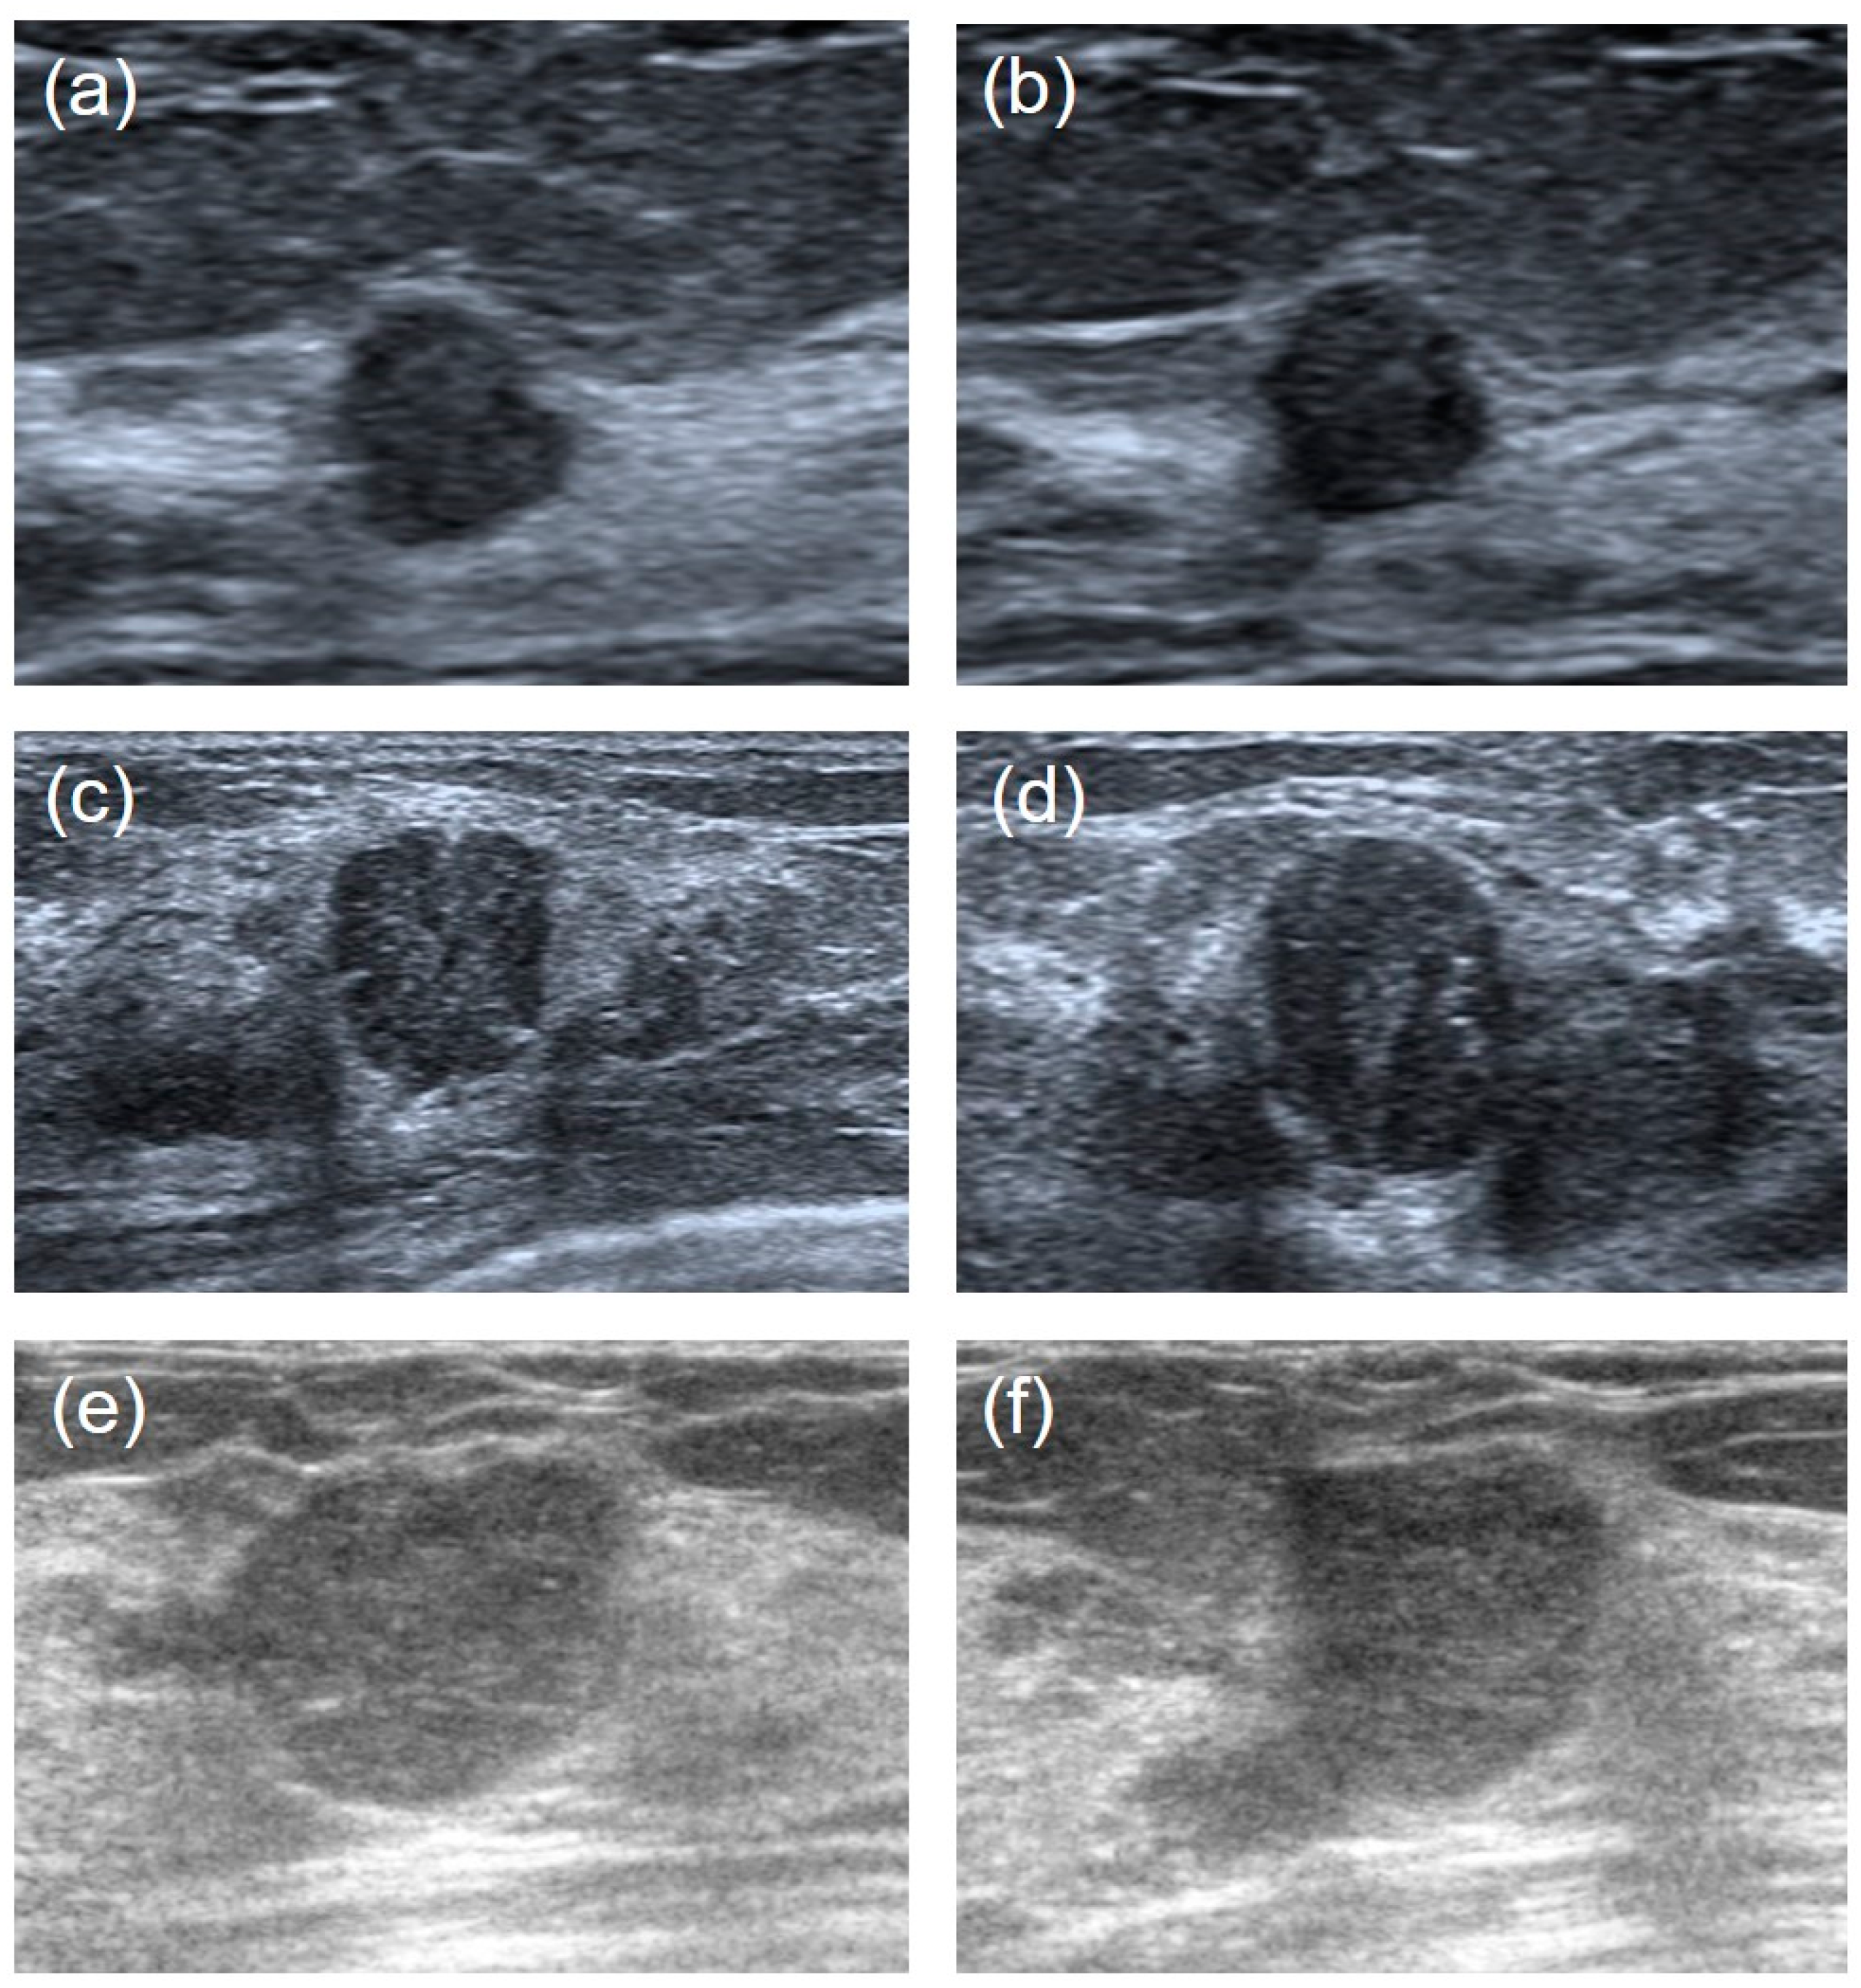

- Image enhancement—the grayscale transformation function was used to enhance the contrast between the foreground and the background of US images. The image enhancement can improve image quality, enrich information, and enhance image interpretation and the recognition effect (Figure 2).